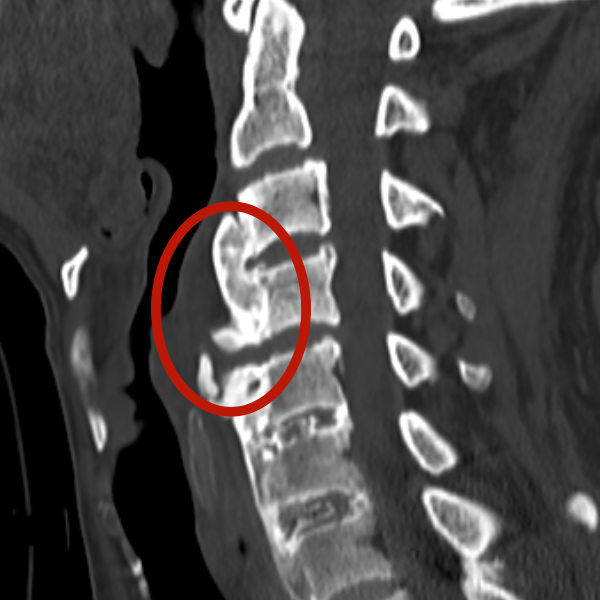

【颈椎出现增生钙化】

屋漏偏逢连夜雨。进一步检查发现,林大爷还患有罕见的DISH病——弥漫性特发性骨肥厚综合征。这种多见于中老年人的慢性退行性疾病,会让脊柱的韧带、肌腱逐渐钙化骨化,就像用“胶水”把颈椎关节牢牢粘住,不仅导致脊柱僵硬疼痛,更让他的颈椎活动度严重受限。

“颈椎本身有外伤压迫,又加上DISH病导致的大面积钙化粘连,相当于‘伤上加伤’,治疗难度直接翻倍。”张正茂副主任医师坦言,粘连的颈椎就像生锈的零件,任何不当操作都可能引发严重并发症。